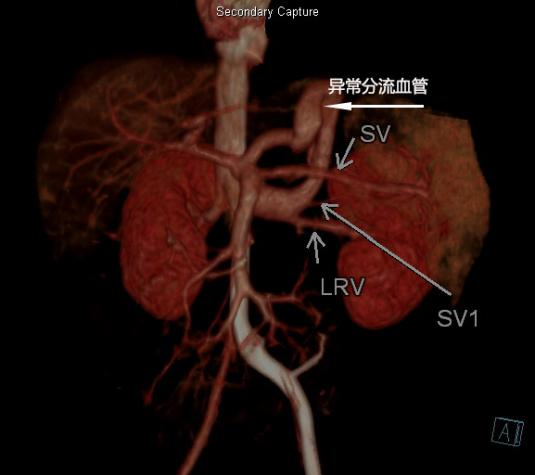

患儿入院后,小儿外科联合小儿重症医学科、医学影像科、超声医学科、麻醉手术科制定了详细的治疗方案。医学影像科马睿主任医师、李宁副主任医师通过CT三维重建获得了清晰的异常血管走形图像,超声医学科王铁铮副主任医师明确了异常分流血管的位置和分流量。小儿普外科团队进行了充分的术前讨论,制定了详细的手术方案和预案。

患儿6月CTV

医学影像科通过CT三维重建获得了清晰的影像,明确了先天性门体静脉分流的类型。该患儿门脉主干发育较细,门静脉左支发育良好,右支纤细,主干侧壁有一粗大的分流静脉,沿肝左叶缘-胃间隙向左上方迂回走行,在近膈肌顶处向下折返,与左肾静脉汇合后汇入下腔静脉,最宽处约7.1mm,最窄处约4.2mm,超声测量分流量约43cc/min,为先天性肝外型门体静脉分流(Abernethy Ⅱ 型)。小儿重症医学科、小儿心脏科通过精心治疗,成功纠正了心动过速、低血糖、高血氨、肺动脉高压、呼吸困难等情况。同时,小儿外科在吴荣德主任的主持下,多次组织讨论,制定了详细的手术方案和预案。患儿治疗23天后顺利出院。